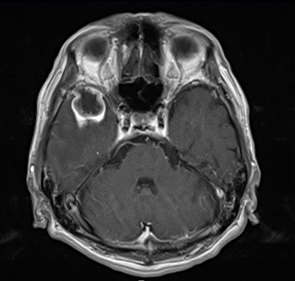

造影MRIで方針決定となる(個数・大きさは予後規定因子になる)。

造影MRI所見:リングエンハンスメント見られる。